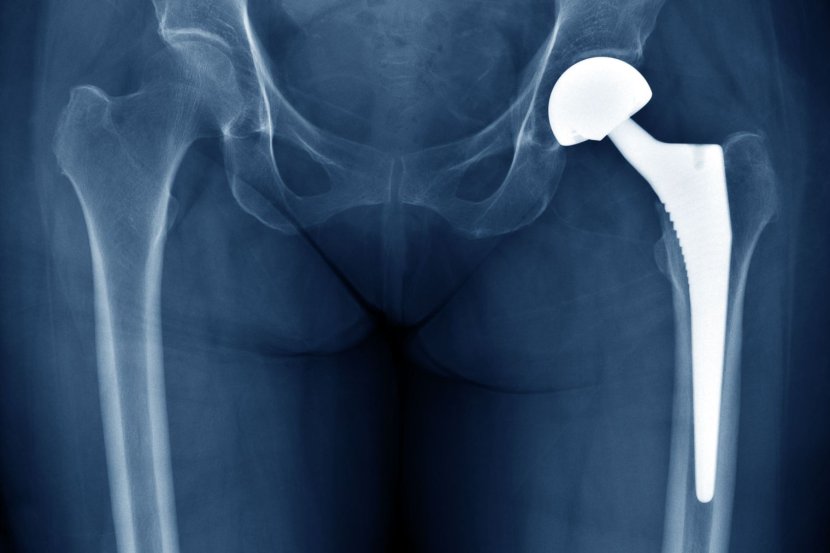

Operacija zamene kuka jedna je od najčešćih ortopedskih operacija koje se obavljaju u Sjedinjenim Državama svake godine i donela je olakšanje milionima koji su patili od bolnih stanja poput osteoartritisa ili reumatoidnog artritisa. Ali uprkos razvoju događaja u poslednjih nekoliko decenija, procedura i dalje nosi potencijalno ozbiljne rizike za neke pacijente, posebno one kojima su ugrađeni implantati kuka metal na metal (MOM).

MOM implantati su oni kod kojih su „loptica” i „utičnica” zgloba kuka napravljeni od legure koja uključuje kobalt i hrom. Sa trenjem koje nastaje usled normalnog habanja, metalne čestice se izbacuju u okolna tkiva i krvotok. Akumulacija ovih čestica može dovesti do štetne metaloze (toksičnost metala) ili kobaltizma od ispuštenih čestica kobalta. Ovo, dalje, može da dovede do simptoma u rasponu od smrti tkiva i gubitka kostiju do neuroloških komplikacija koje imitiraju Alchajmerovu bolest.

Operacija totalne zamene kuka (THR), koja se naziva i totalna artroplastika kuka, postoji skoro jedan vek. Trenutno se smatra jednom od najsigurnijih i najuspešnijih ortopedskih operacija. Prema Američkoj akademiji ortopedskih hirurga, više od 450.000 THR operacija se obavlja godišnje u Sjedinjenim Državama. Tradicionalne zamene kuka uglavnom koriste metalnu „loptu” zajedno sa polietilenskom (plastičnom) oblogom ili „utičnicom”. U skorije vreme, različite kombinacije metalnih legura, umreženog polietilena i keramike su postale najšire korišćene.

Implantati metal na metal (MOM) prvi put su korišćeni 1966. godine i brzo su stekli popularnost. Smatralo se da imaju nekoliko prednosti u odnosu na konvencionalno korišćene implantate od metala na polietilenu, uključujući manje „habanja”, veću izdržljivost i mogućnost korišćenja većih femoralnih glava („loptasti” deo kuglice i utičnice), što bi moglo da obezbedi veću stabilnost i obim pokreta kod pacijenta, kao i manju šansu za dislokaciju. Ovo je učinilo implantate metal na metal posebno atraktivnom opcijom za mlađe i visoko aktivne pacijente.